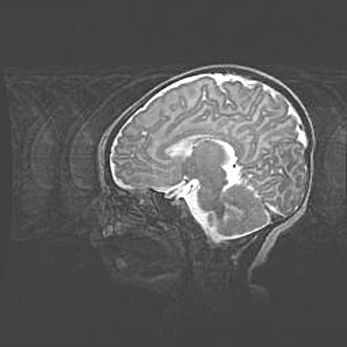

Аномалия Денди-Уокера. Признаки гипоплазии мозолистого тела.

Возраст: 5 месяцев 3 дня

Вес: 5550 г

Пол: мужской

Окружность головы: 39 см

Срок гестации: 40 недель

Аномалия Денди-Уокера – это порок развития головного мозга, для которого характерна триада симптомов: гипотрофия или аплазия червя мозжечка и/или полушарий мозжечка, расширение четвёртого желудочка с формированием ликворной кисты задней черепной ямки, гипертензионная гидроцефалия различной степени.

Гипоплазия мозолистого тела относится к дефектам внутриутробного этапа развития мозговой ткани, возникающим в процессе закладки структур головного мозга, что происходит на начальных этапах развития эмбриона.